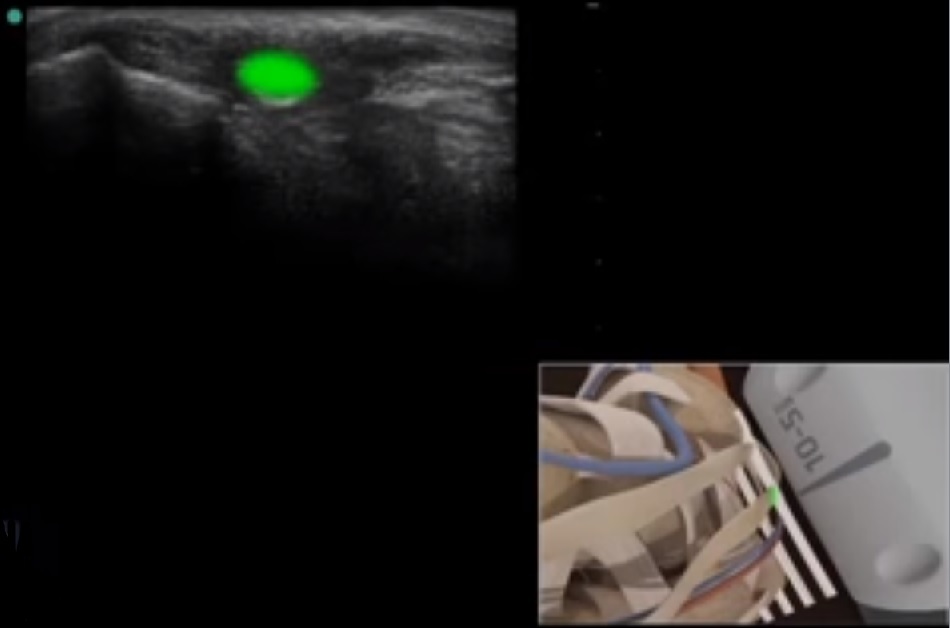

Bild: Fuß und Sprunggelenk, Sehne des Flexor digitorum longus

Markierter Bereich: Flexor digitorum longus